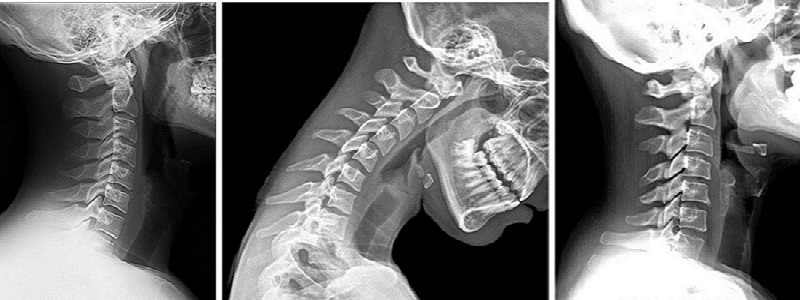

Telefon ve bilgisayar kullanımı, omurganın duruş ve biyomekaniğini olumsuz etkileyerek boyundaki fizyolojik eğriliğin deformasyonuna yol açmaktadır. Cep boyun hastalığının şiddeti kişiden kişiye değişiklik gösterebilir. Hafif vakalarda boyun kaslarında ağrıya, ilerlemiş vakalarda ise baş ağrısı, kollarda karıncalanma ve uyuşma, boyun omuru disk hasarlarına yol açabilmektedir.

Daha ileri durumlarda bu yeni teknoloji ürünü aletler, omurlar arasındaki disk ekleminin yıpranmasına ve boyun fıtığı oluşmasına neden olabilmektedir. En sık görülen şikayetler; boyun ağrısı, baş ağrısı, boyun kaslarında spazm, tetik nokta, gergin bant gibi kulunç benzeri sertlikler, kollarda uyuşukluk, karıncalanma, kamburluk, başın vücuda ağır gelen hissi, gece uyku kalitesi düşüklüğü olarak ortaya çıkabilmektedir. İlk başta bu belirtilerin duruştan kaynaklandığını kişi anlayamadığından, günlük aktivitelerinde boynun bu duruş bozukluğunda kalması uzun süreçlerde devam eder ve zamanla ağrı da şiddetlendikçe, kişi buna çözüm aramaya başlar; ancak yaşam alışkanlıklarının değiştirilmemesi sebebiyle kendi kendine iyileşme gibi bir yöntem bulması zorlaşır.